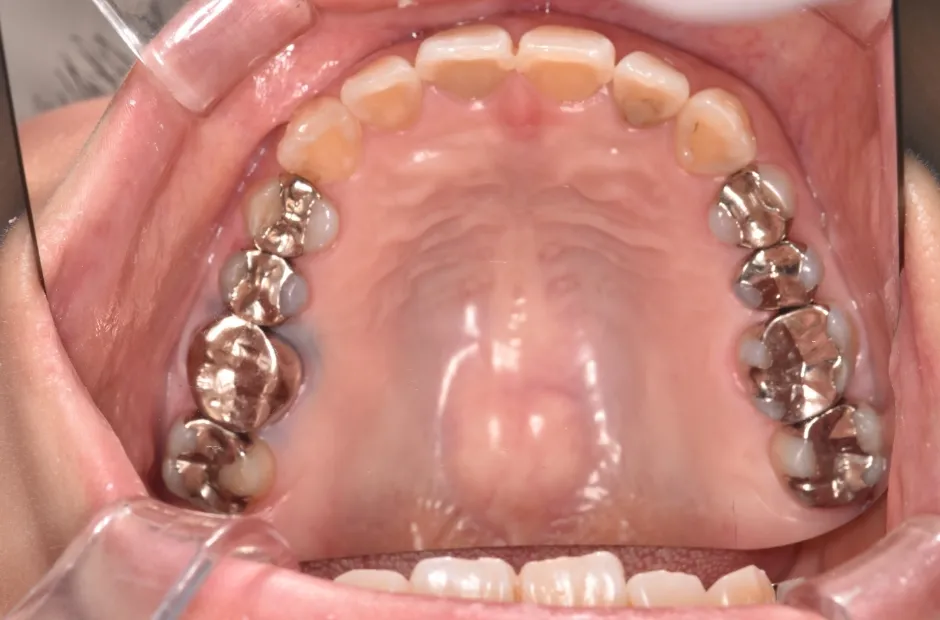

叢生

| 診断名・主訴 | 叢生 |

|---|---|

| 年齢・性別 | 43歳・女性 |

| 治療期間・回数 | 2年7か月 27回 |

| 治療に用いた主な装置 | 舌側矯正 |

| 抜歯部位 | 両顎4,4 |

| 治療費 | 100万円(税抜) |

| リスク・副作用 | 装置による違和感・疼痛・歯肉退縮・歯根吸収・虫歯のリスクなど |

治療前